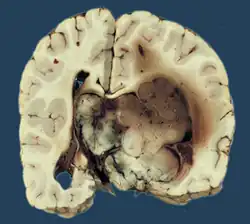

Choroid plexus tumors are divided into three categories by the World Health Organization (2016):[9] papillomas (grade I), atypical tumors (grade II), and carcinomas (grade III). Less than two mitotic figures per 10 high power fields are present in CPPs, two to five are present in atypical ones, and more than five are present in carcinomas. The tumors are visible as pink, soft, spherical lumps with erratic projections and considerable vascularity.

The tumor is neuroectodermal in origin and similar in structure to a normal choroid plexus. They may be created by epithelial cells of the choroid plexus. Papillary fronds lined by bland columnar epithelium are visible under the microscope. Normal absences include mitotic activity, nuclear pleomorphism, and necrosis.[10] Tumors have positive immunohistochemistry for cytokeratin, vimentin, podoplanin, and S-100.[11] Up to 20% of choroid plexus papilloma patients may test positive for glial fibrillary acidic protein (GFAP).[12] Studies have found that fourth ventricle cancers express more S100 than lateral ventricle tumors, and older patients (over 20 years) express more GFAP and transthyretin than younger patients.[13] Some individuals with choroid plexus papilloma have germline TP53 gene mutations, according to genetic analyses.[14] These cancers rarely exhibit nuclear p53 protein positivity. Aicardi syndrome, hypomelanosis of Ito, and 9p duplication are syndromic correlations of choroid plexus papilloma.